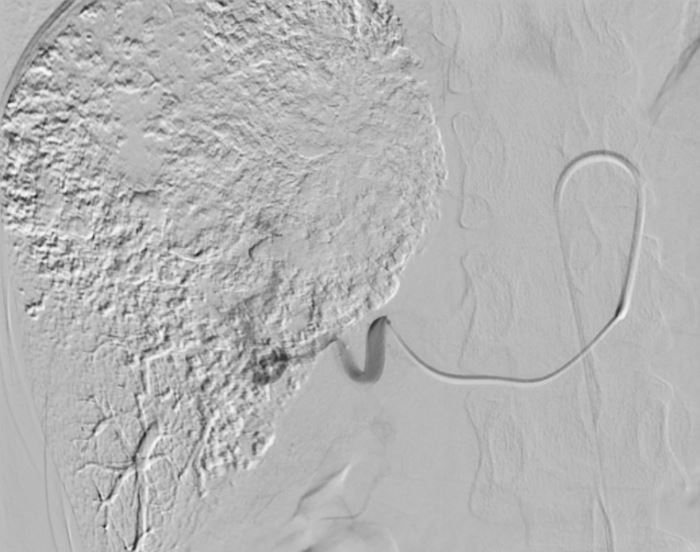

近日,潞河医院介入疼痛科为一名巨大肝血管瘤女性患者成功实施了介入栓塞治疗。患者梁女士今年49岁,体检时发现肝右叶血管瘤,最大径约9.6cm,且位于肝脏边缘,虽然破裂的几率较小,但一旦自发或外伤性破裂可能会给患者带来致命后果。梁女士入院后,介入疼痛科主任韩洋带领团队认真评估了术前影像学检查,并完善各项检验,排除治疗禁忌后,讨论制定了治疗方案。在与梁女士及家属充分沟通后,介入团队为其成功实施了微创介入栓塞治疗。术中腹腔干及肝动脉造影可见肝右叶巨大肿瘤染色,随着栓塞治疗的持续,可见该血管瘤内药物逐渐沉积,治疗完毕后再次造影显示原肿瘤供血动脉已封堵。手术成功完成,达到了治疗目的。术后,梁女士没有出现任何不良反应,现已顺利出院。

治疗后的造影图